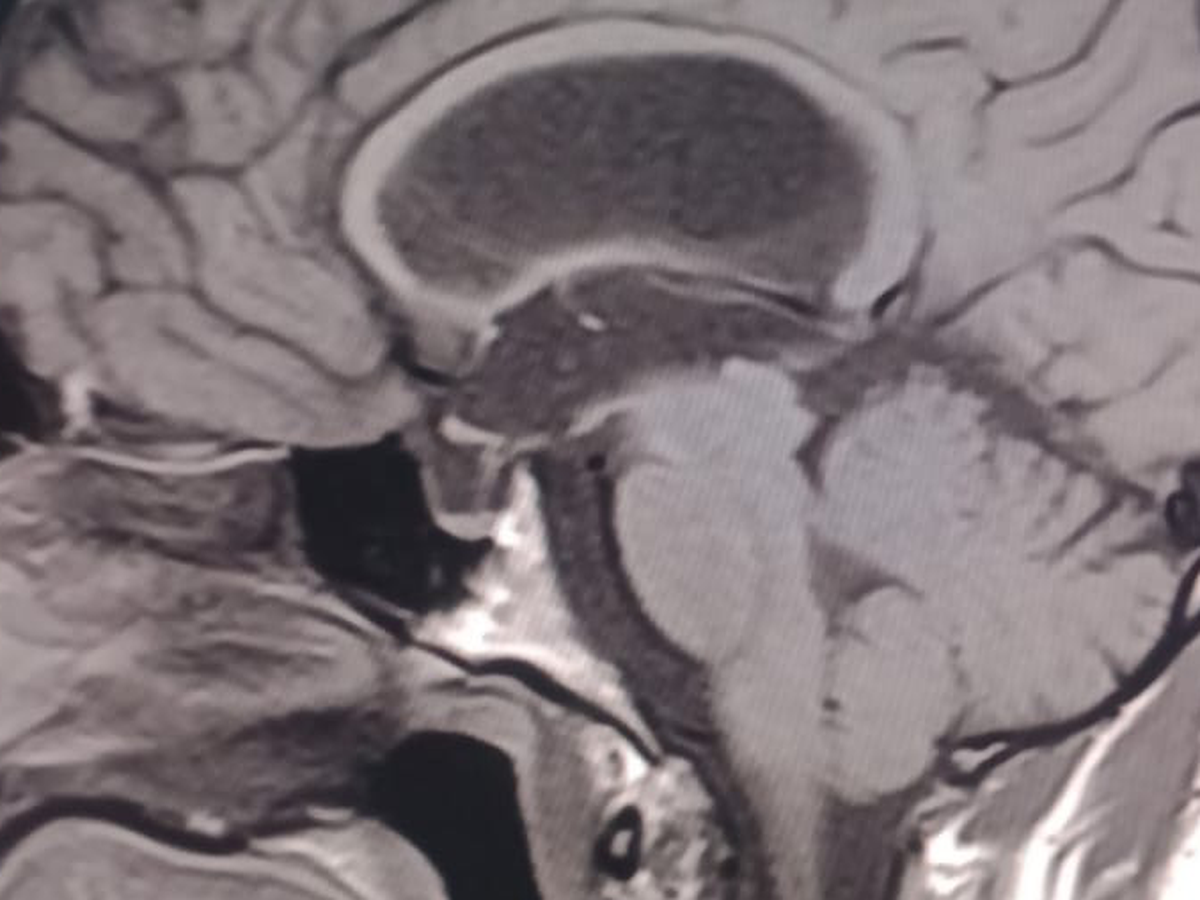

Our dear Cesar Eduardo Rodríguez Ortiz has been fighting seizures since he was just two years old, after suffering a head injury as a baby. Despite years of struggle, his strength and spirit have never faded.

On October 17, 2025, Cesar underwent a major brain surgery to help control his severe epilepsy. By God’s grace, the surgery went well, and he is now beginning his road to recovery.